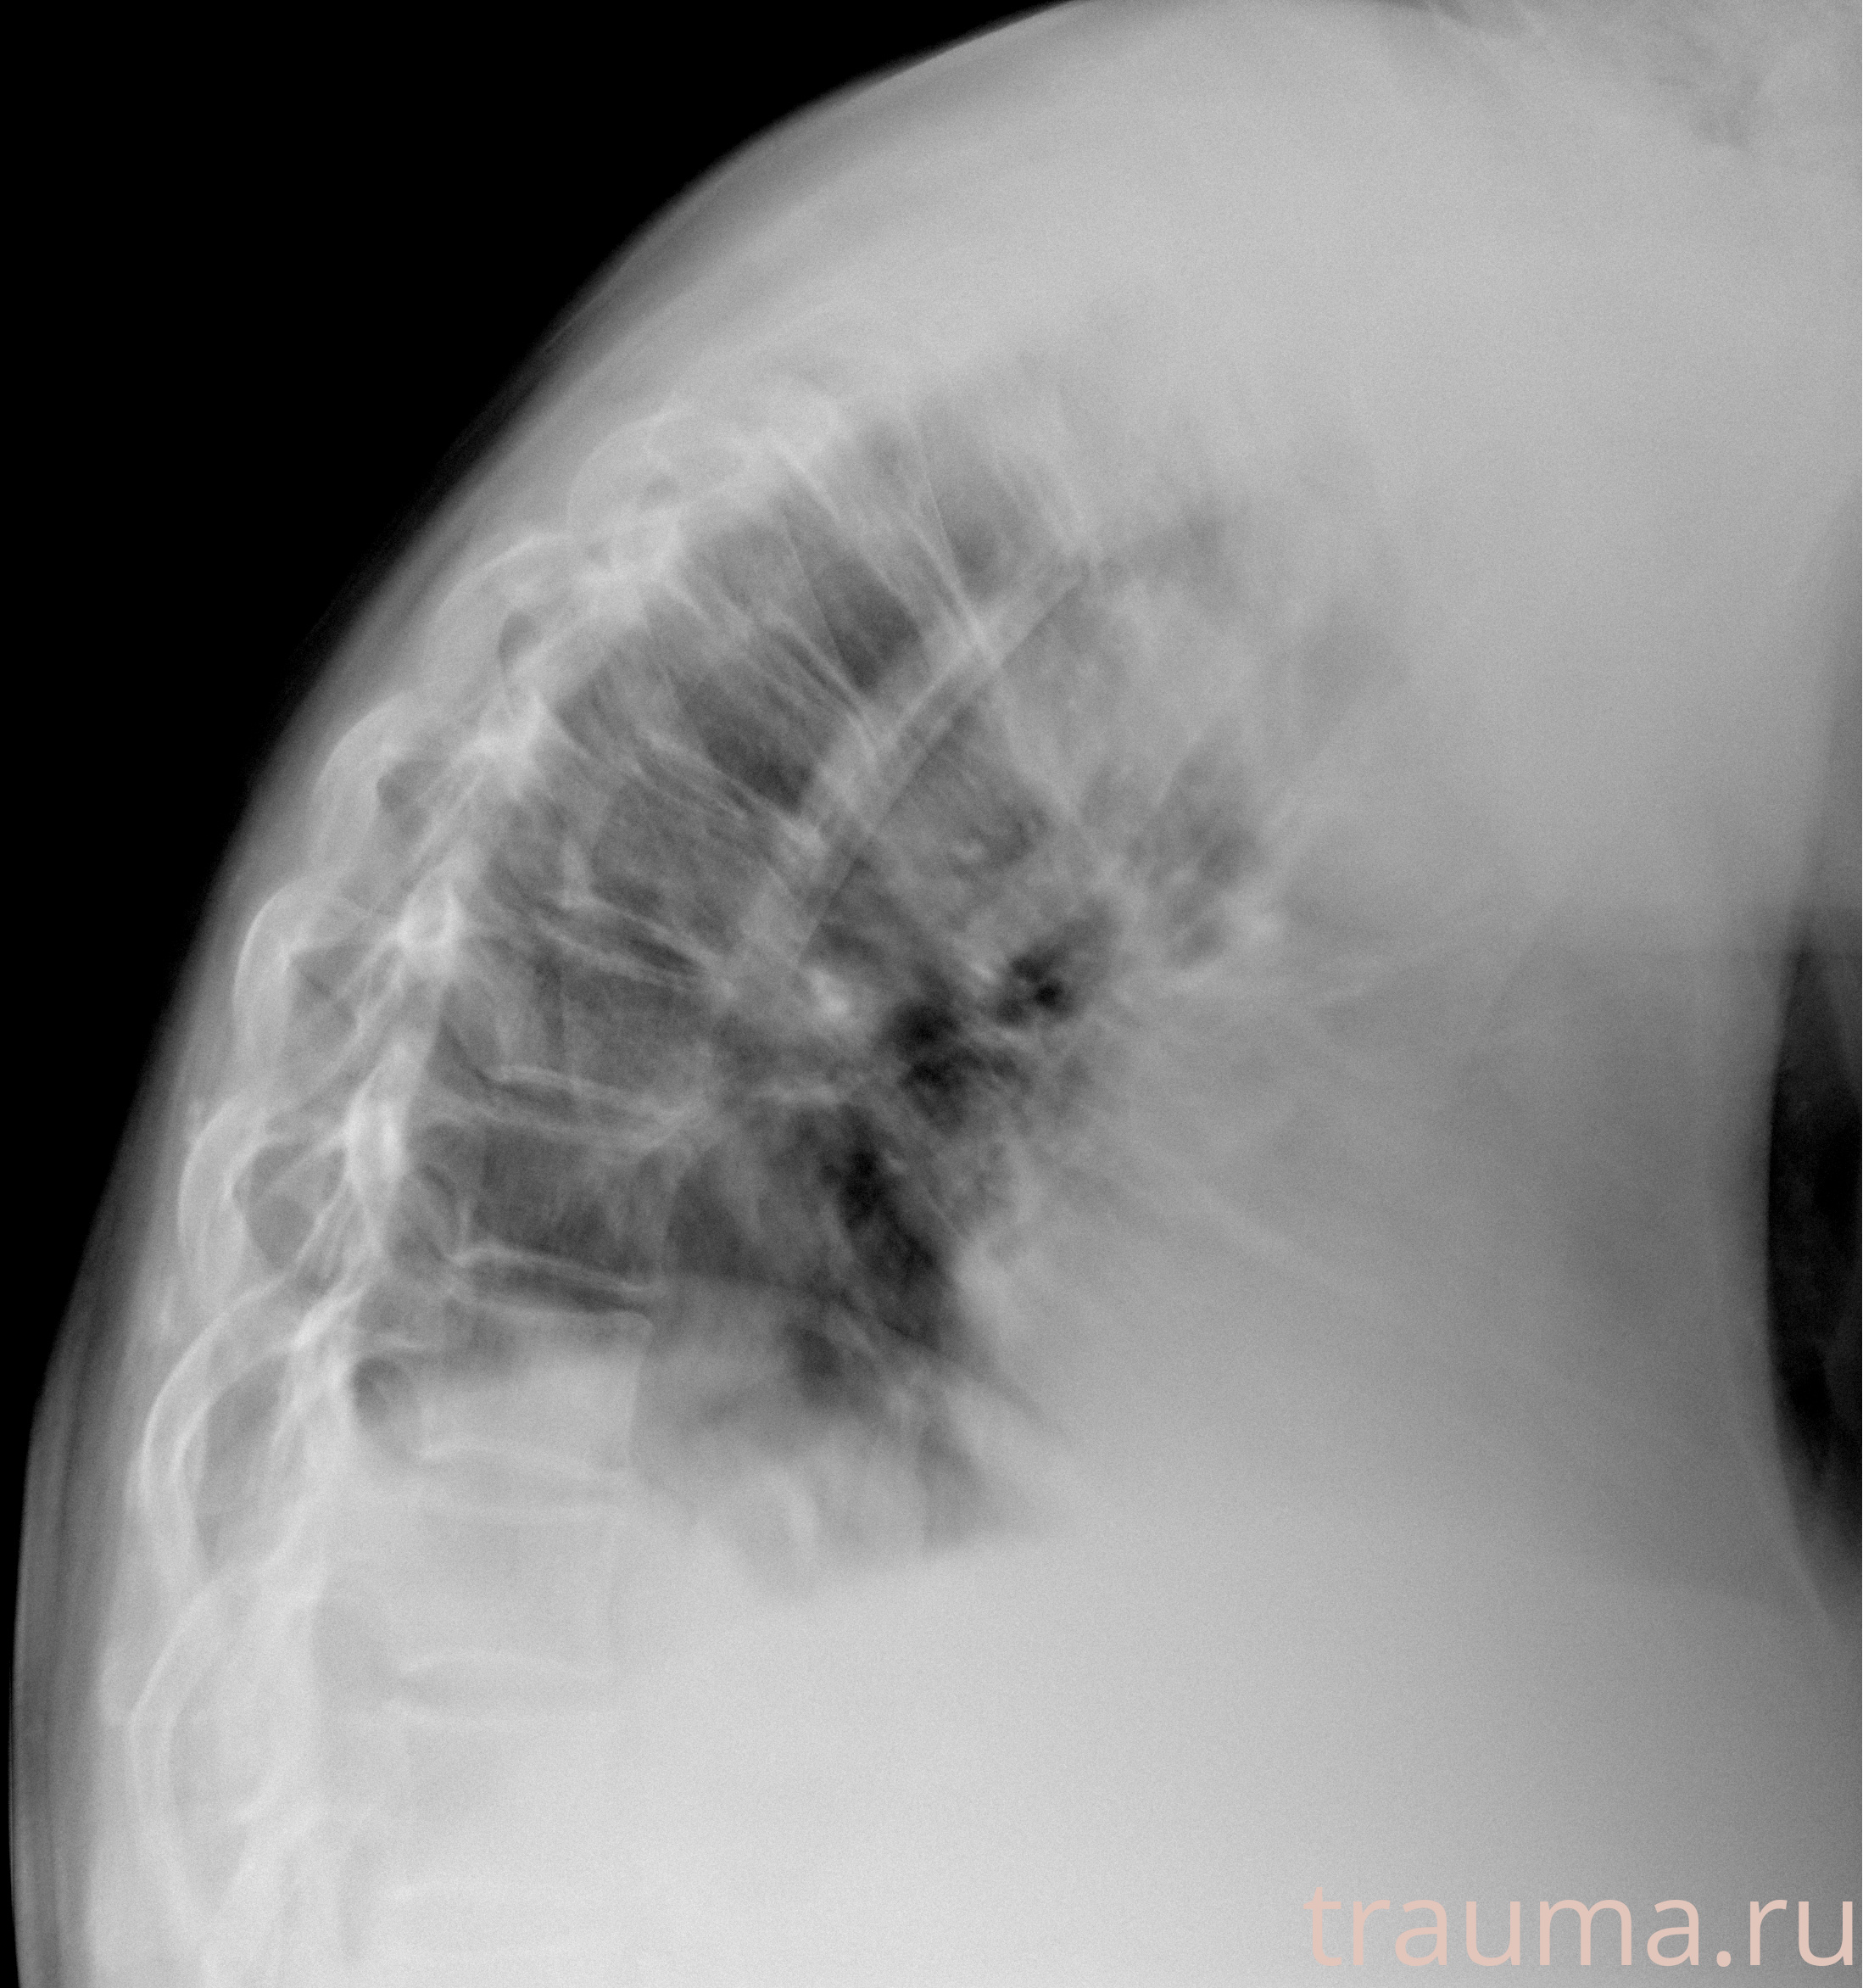

Рентгенограммы

Рентген на дому: по вашему адресу приезжает врач-рентгенолог, травматолог-ортопед с мобильным рентгеновским аппаратом, проводит диагностику травмы или заболевания, делает необходимые рентгенограммы, дает рекомендации по дальнейшему лечению. Получить качественные снимки в домашних условиях возможно благодаря уникальной методике, разработанной МосРентген Центром для института  Склифосовского